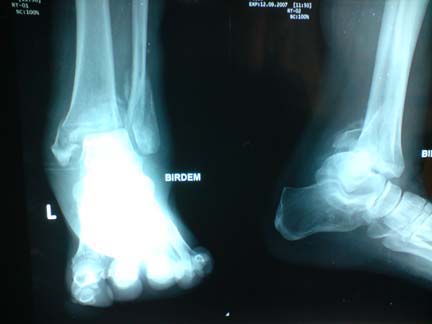

A 65-year-old man with type 2 diabetes of eight years duration was referred to BIRDEM hospital OPD with unexplained pain and swelling in his left foot and ankle. He was known to have retinopathy, neuropathy and peripheral vascular disease. His glycaemic control was poor. Pain and swelling in the ankle and foot had started six months previously. He could walk with the help of a crutch. His ankle was deformed and unstable, and sensation in the foot including pain and touch was reduced. He had been investigated by his general practitioner. As there was no history of trauma, his physician did not get a x-rays done. Alkaline phosphatase, C-reactive protein, urate level were slightly elevated and rheumatoid factor was normal. Possible diagnosis was considered as gout and cellulitis and several courses of antibiotics were prescribed.

X-rays of the ankle and foot were done in BIRDEM and revealed gross osteopenia, soft tissue swelling and fracture-dislocation of the left ankle with bony fragmentation and callus formation at the fracture site (Fig.3). His inflammatory markers of the blood were unremarkable. The clinical picture and investigations were considered compatible with a Charcot arthropathy of left ankle. Arthrodesis of the ankle was done with a ‘T’ shaped plate and five screws and immobilised with a short leg plaster cast. His ankle fused over the next twelve months.

Fig. 3. Pre-operative X-ray:Fracture and dislocation in a left ankle Charcot joint